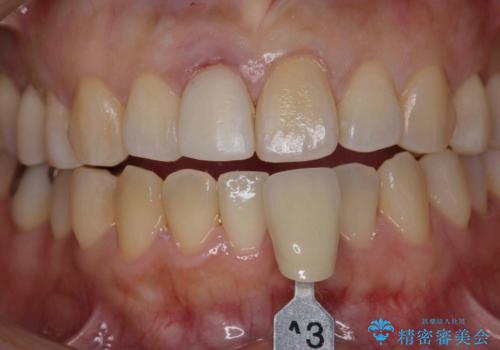

オーダーメイドで造る、自然な前歯セラミッククラウン

- 幼少期に前歯をぶつけて歯が折れ、神経の治療・クラウン治療を行った。グラつきと見た目の改善を希望して来院されました。

精密な仮歯をいれ、歯周組織を整えるとともにファイバーコア築盛、シェードテイキングを行い見た目に自然なジルコニアクラウンを製作していきます。

ジルコニアクラウンの中でも当法人のグレードの高い、スペシャル・エクセレントプランはオーダーメイドで色調を合わせることで周囲の歯に馴染んだ自然な歯を製作することのできるプランです。